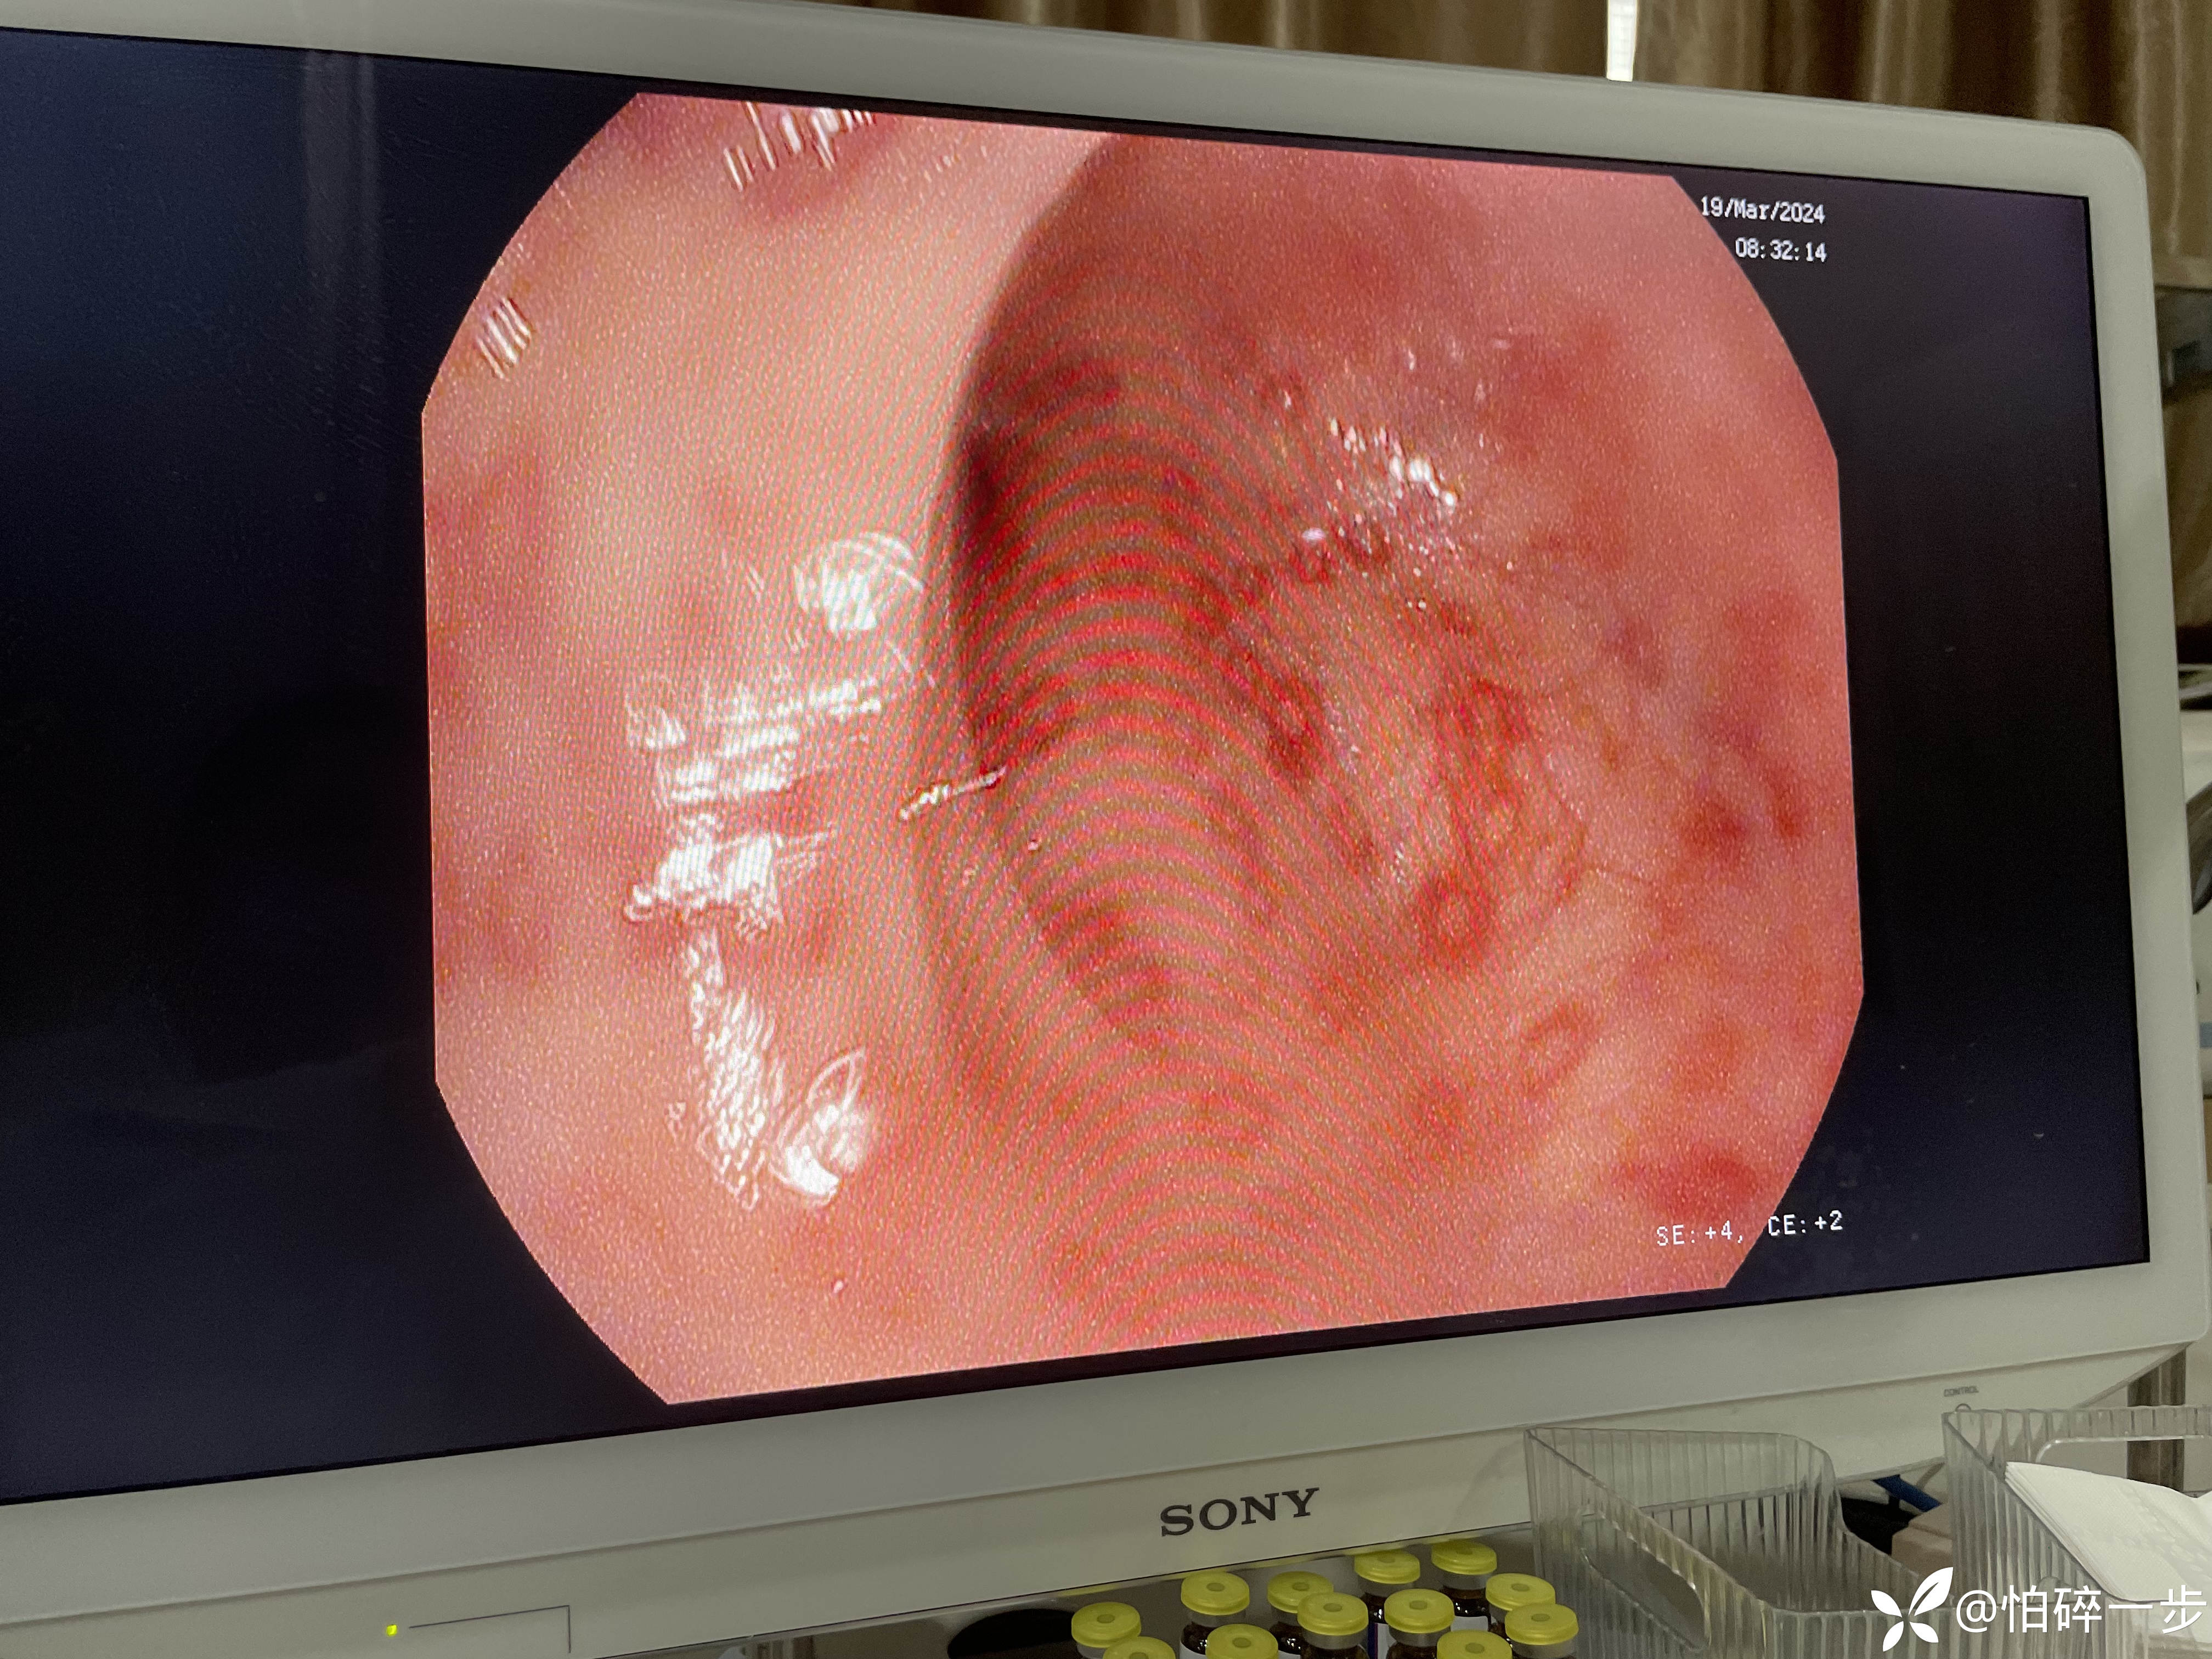

30岁,女性,2年前体检肠镜无异常。1月前无诱因突发脐周剧烈疼痛,之后出现大便改变,大便次数3-4次/天,大便变细。1周前再次出现左下腹剧烈疼痛,大便5-6次/天,大便不成形,排便结束时混有黏液,1周以来下腹部隐痛不适,有2次解黑便史,未进行治疗。本次门诊肠镜检查提示如下。请问各位站友意见如何?